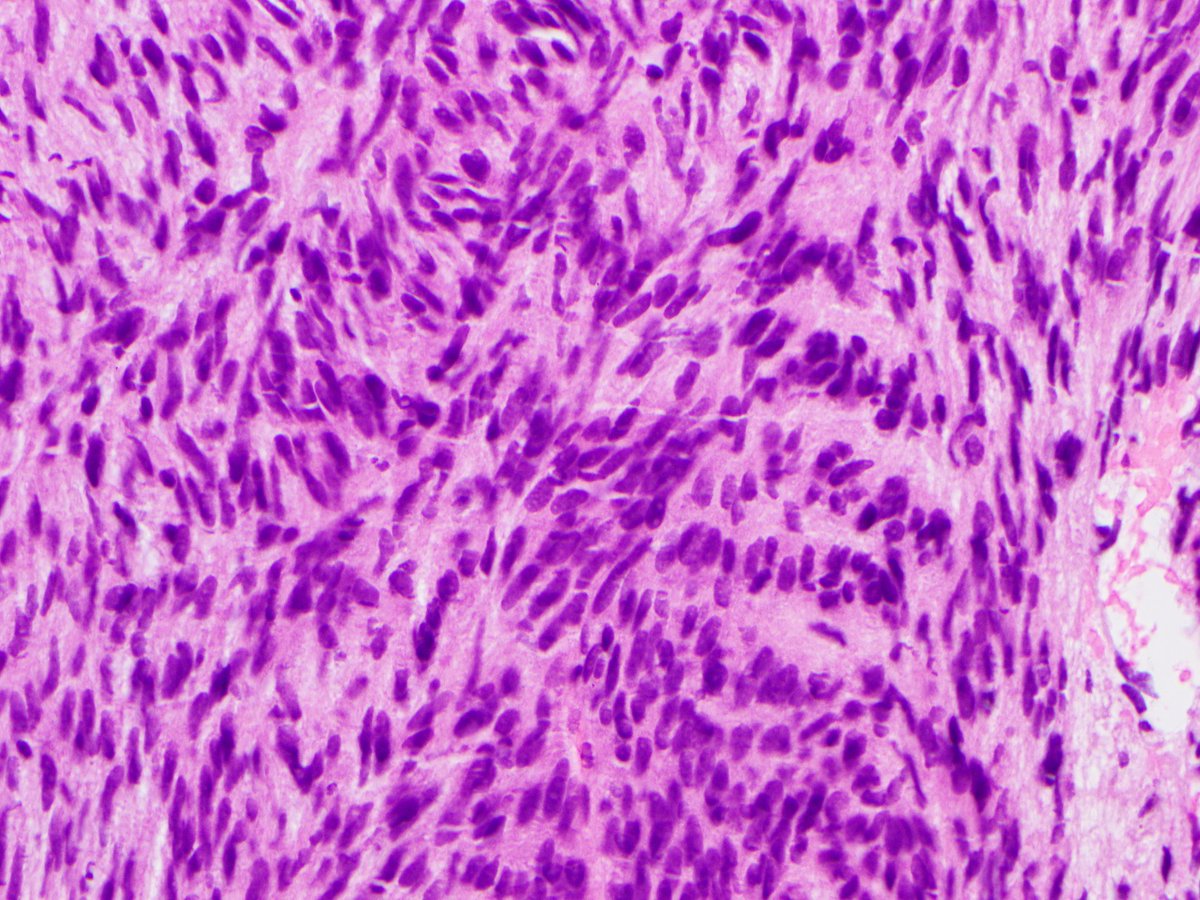

24yo F, 2cm wrist lesion. #pathology #pathtwitter #BSTpath #pathboards Einstein Montefiore Pathology @histiocytosisX Jason L. Hornick, M.D., Ph.D. Tristan Rutland MBBS FRCPA IFCAP Brian Cox, MD, MAS Vish Killari MD MPH Celina Stayerman MD Adam L. Booth, MD Jerad Gardner, MD Olaleke Folaranmi